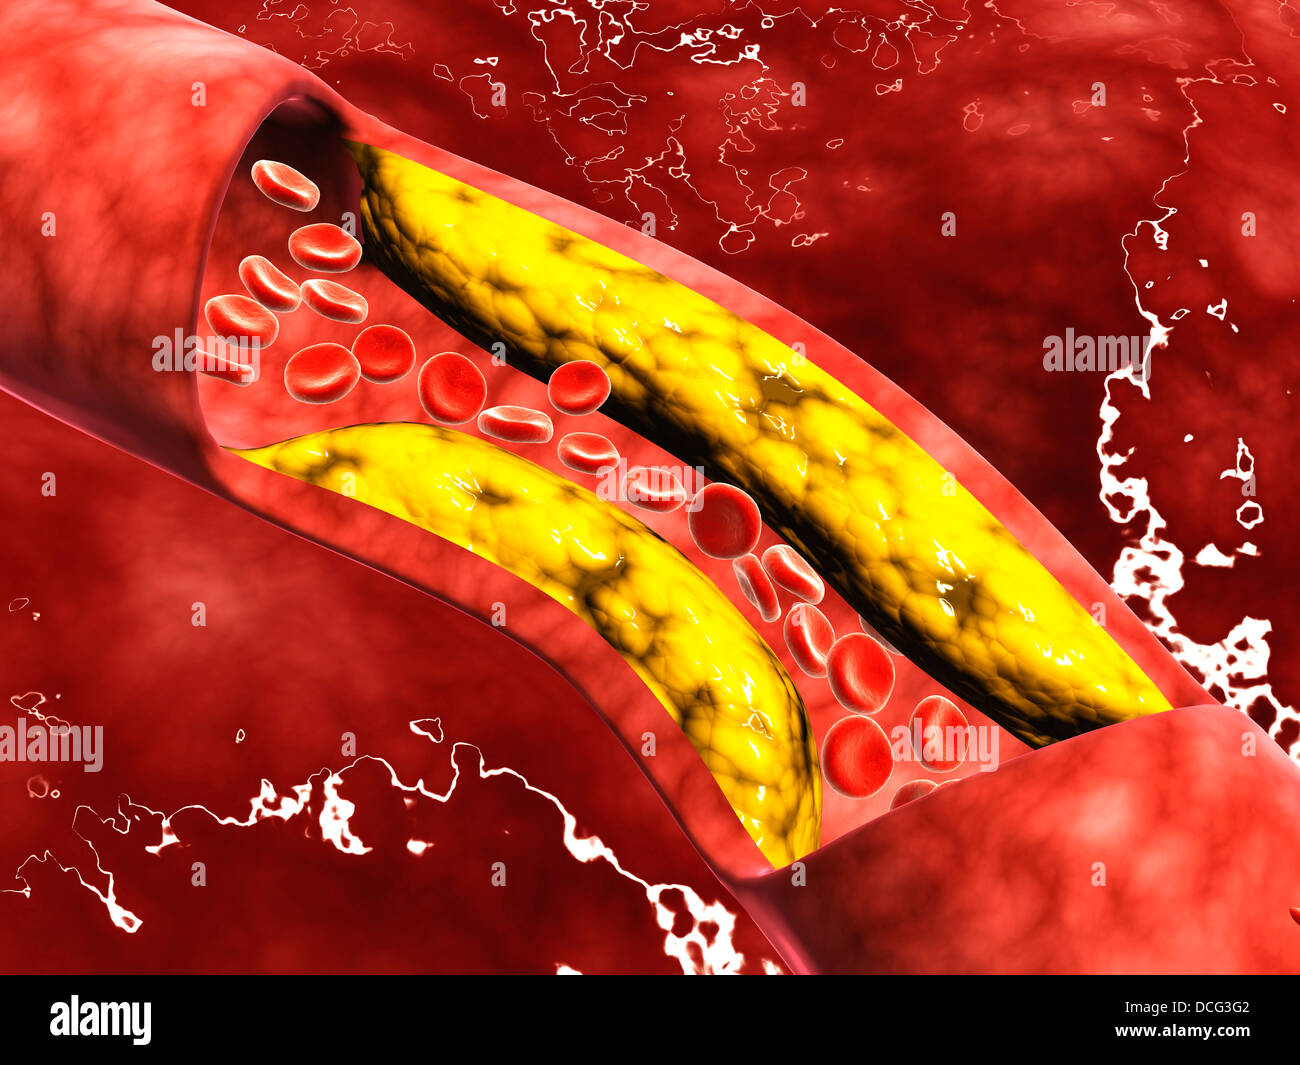

Microscopic view of fat plaque inside the artery. Stock Photohttps://www.alamy.com/image-license-details/?v=1https://www.alamy.com/stock-photo-microscopic-view-of-fat-plaque-inside-the-artery-59361010.html

Microscopic view of fat plaque inside the artery. Stock Photohttps://www.alamy.com/image-license-details/?v=1https://www.alamy.com/stock-photo-microscopic-view-of-fat-plaque-inside-the-artery-59361010.htmlRFDCG3G2–Microscopic view of fat plaque inside the artery.